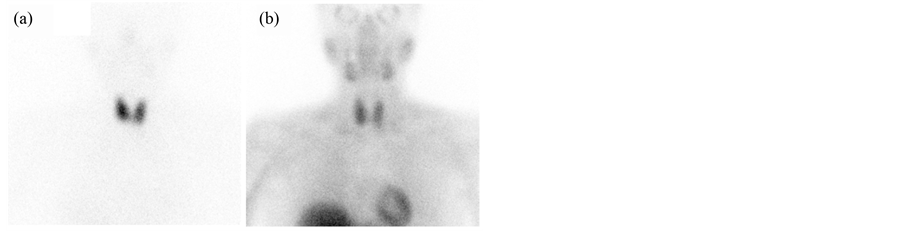

Retrospective image interpretation was independently performed by 3 nuclear medicine trainees and 2 experienced nuclear medicine physicians blinded to all clinical information. For the purpose of analysis, the neck was divided into 4 regions of interest (ROI) relative to the thyroid; right upper, right lower, left upper, and left lower. For each of the 4 regions, the readers rated their confidence that an abnormal parathyroid gland was present on a five-point scale: 1) definitely absent, 2) probably absent, 3) equivocal, 4) probably present, and 5) definitely present. Two sets of images were reviewed. The first set of images consisted of side-by-side 99mTc- sestamibi and 123I-NaI images for simple visual comparison (Figure 1). The second set of images included the 99mTc-sestamibi and 123I-NaI planar images with addition of the 4 digital subtractions described above (Figure 2). Image interpretation was conducted in a single session; all images of the first set (visual comparison

Figure 1. Simultaneously acquired anterior planar 123I-NaI (a) and 99mTc-sestamibi (b) images over the neck in a patient with primary hyperparathyroidism. There is relatively congruent 99mTc-sestamibi and 123I-NaI uptake without apparent discordant uptake to suggest location of a parathyroid adenoma. In this case, 0 out of 5 reviewers accurately localized the adenoma.